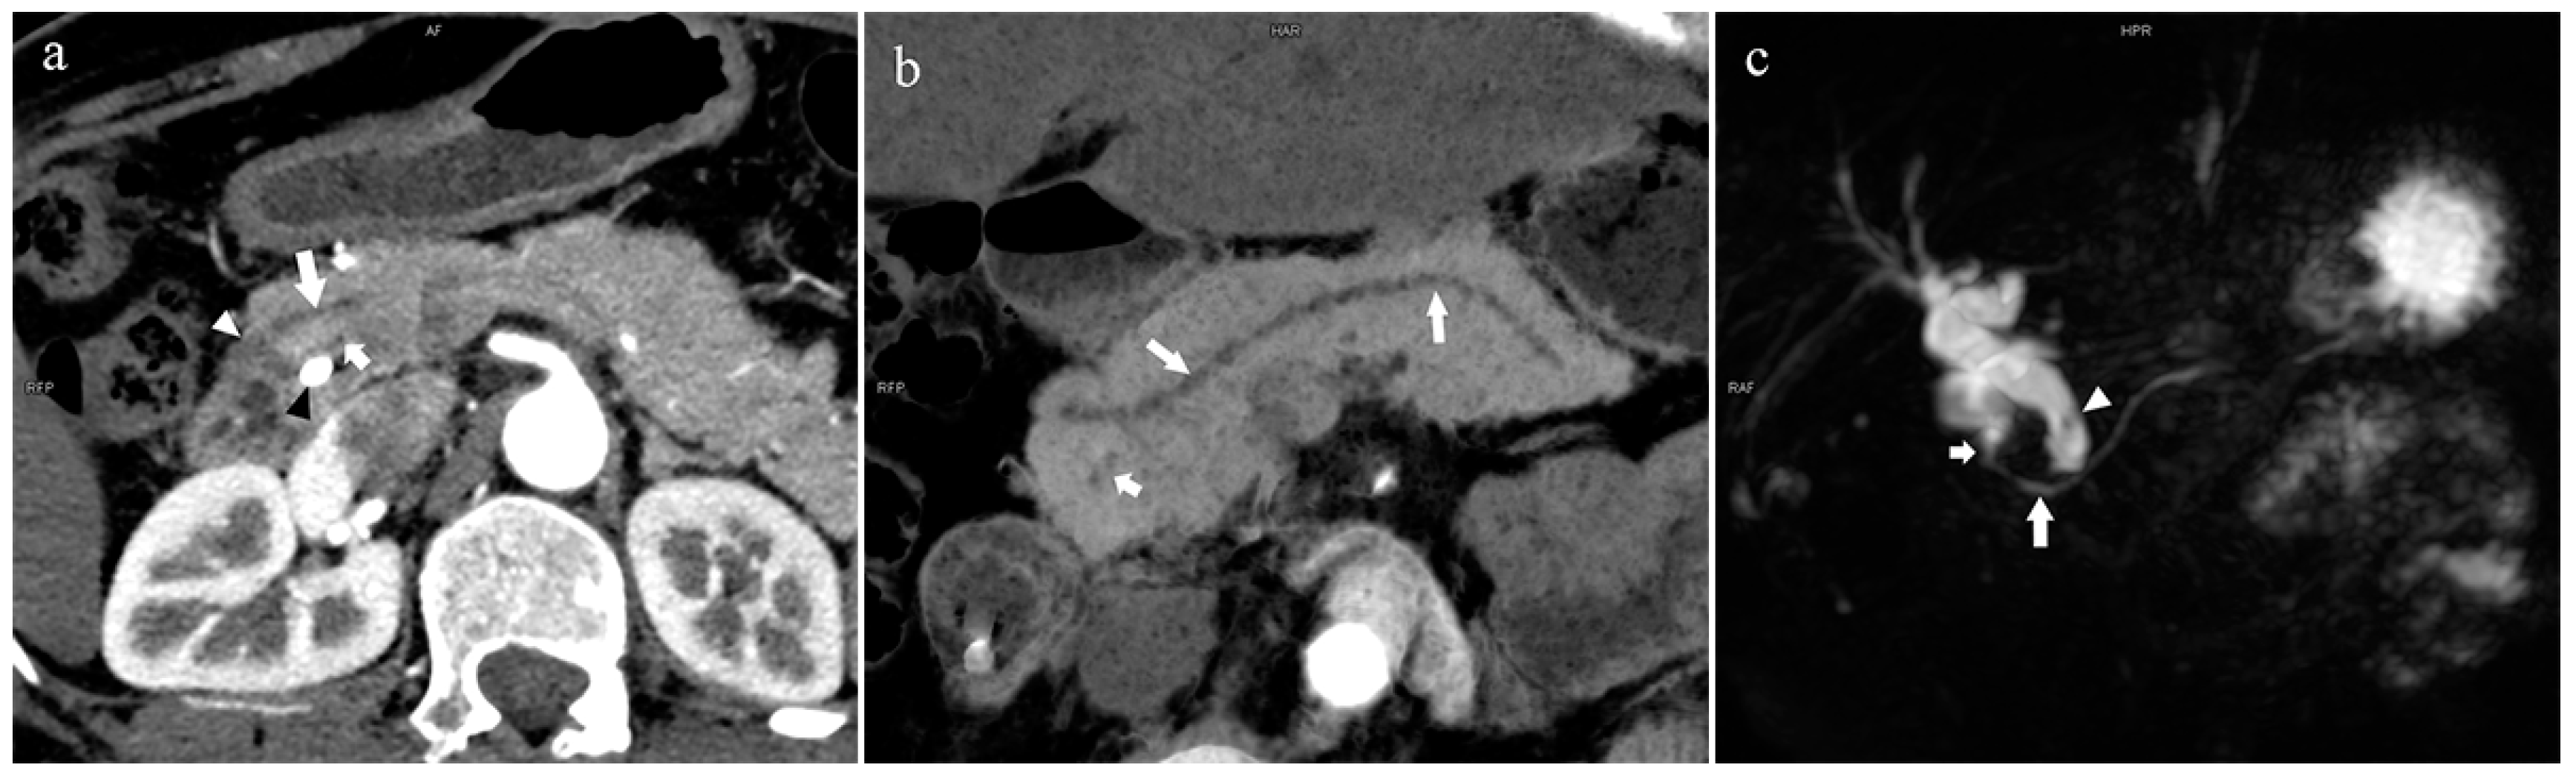

Figure 7.

Complete pancreas division (Type 4a). A 42-year-old female patient with common bile duct stones. (a): MIP [45 keV MEI (+)] shows that the MPD (long arrow) flows into the MiP (arrowhead) and the APD (short arrow) flows into the MP. There is no communication between MPD and APD. The T-tube (black arrow) can be seen in MP and the common bile duct. (b): MinIP [45 keV MEI (+)] more intuitively shows the overall shape of MPD (long arrow) and APD (short arrow). MPD flows into MiP and extends to the tail of the pancreas. (c): Oblique coronal thick slab MRCP image shows MPD (long arrow) flows into the MiP (short arrow) and the APD is not displayed. The stone (arrowhead) is located in the middle and lower part of the common bile duct. MPD refers to anatomically large and functionally dominant ducts.

In the 852 patients, there was a significant difference between the low-keV DECT and MRCP images in observing the pancreatic duct system (p < 0.05), and the mean rank of the former was higher than that of the latter (909.44 > 795.56). Thus, the sharpness of the pancreatic duct images of low-keV DECT is better than that of MRCP. Figure 6 shows that the reconstructed DECT images (MIP and MinIP, 45 keV) could show small ADP (Figure 6a,b), while this was not observed on MRCP (Figure 6c).